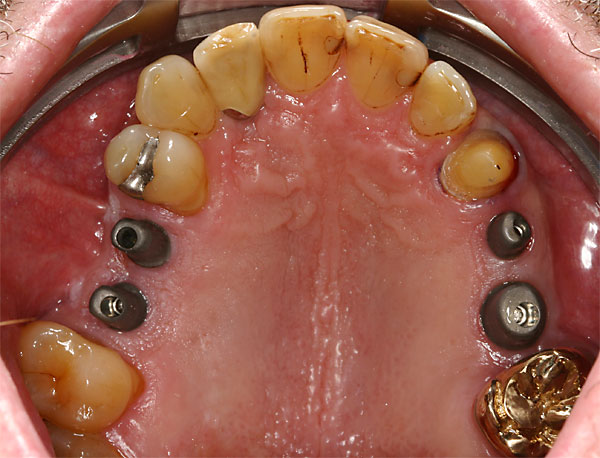

FOTO Totale Prothese im Oberkiefer – Anfangsbefund |

FOTO Abdruckpfosten im Mund zur Übertragung auf das Meistermodell |

Fall: festsitzender Zahnersatz im Oberkiefer auf 8 Implantaten